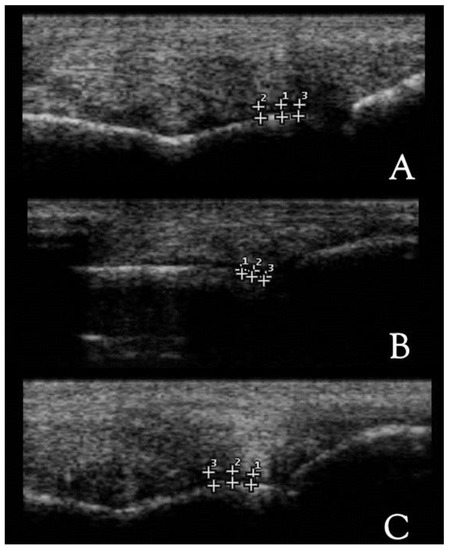

| Cartilage | Normal | Round and smooth in longitudinal section and triangular in cross-section, anechogenic and regular |

| Cartilage Thickness | Sagittal ridge | 0.7–1 mm |

| Medial condyle | ||

| Lateral condyle | ||